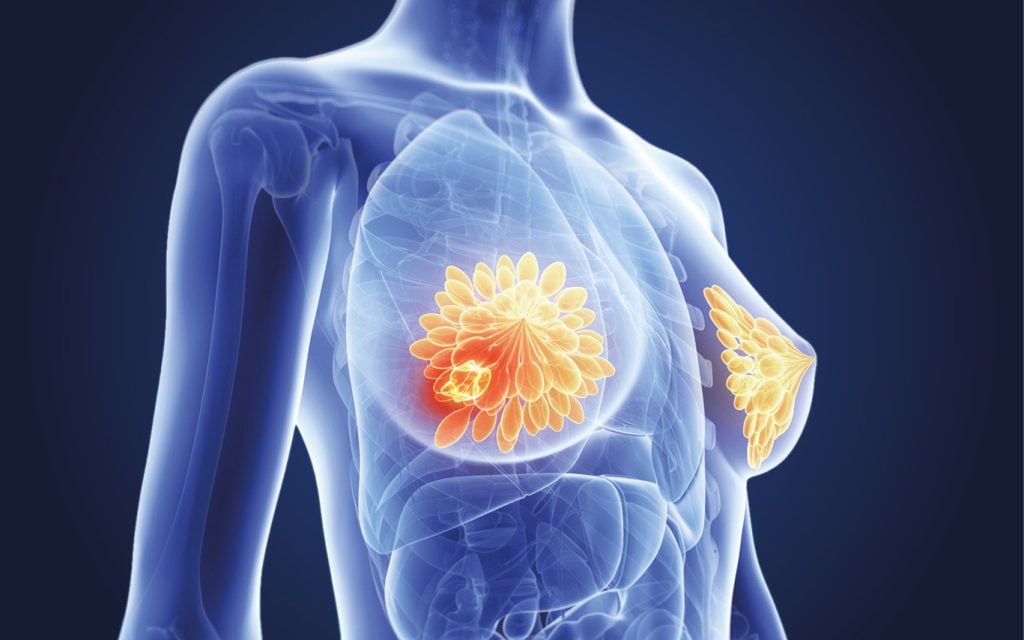

Breast cancer and diet

Whilst there are various factors that predispose a person and increases their risk of developing breast cancer including gender, age, lifestyle, and family history, national screening programmes can detect breast cancer earlier, resulting in better outcomes.

- How diet, nutrition, body fat levels and physical activity impact the risk of breast cancer